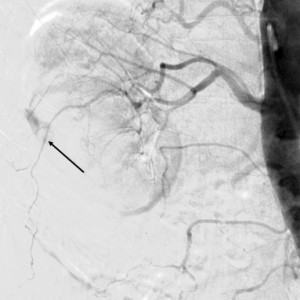

The arterial approach was right femoral, with a 6F introducer sheath. The angiography confirmed the presence of a sub-occlusive stenosis in the right common iliac artery (Figure 1), with important calcification of the terminal aorta and of both common iliac arteries. 5000 IU of unfractioned heparin were given intravenousely. After the passage of a hydrophilic wire through the lesion into the abdominal aorta, a pre-dilatation was made, with a 6 mm diameter balloon. After that we implanted an Express LD stent, 8 mm diameter, 37 mm long and performed a post-dilatation with a 9 mm diameter balloon. The final result was good (Figure 2).

Figure 1. Sub-occlusive stenosis of the right common iliac artery; note the intense calcification of the terminal aorta and both iliac arteries.